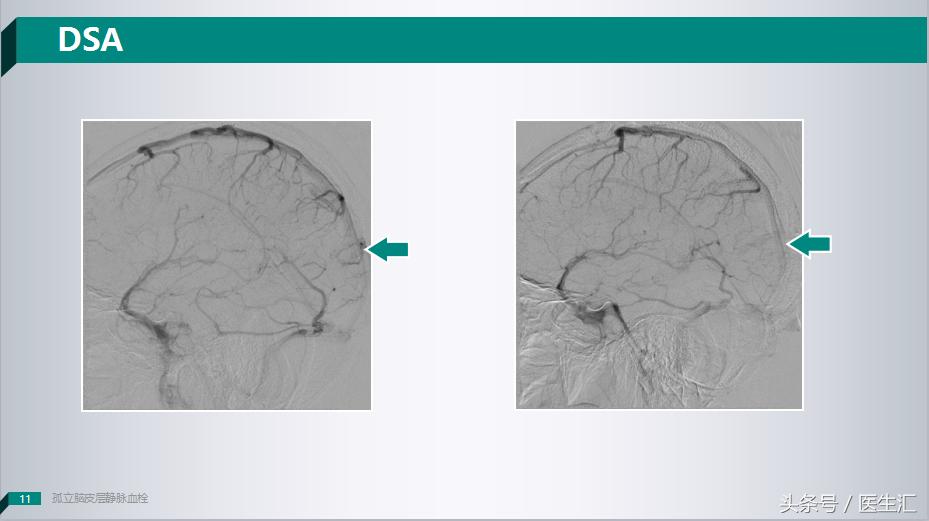

因为这个患者贴近皮层,所以我们就给患者做了一个DSA的检查,我们可以看到这个患者患侧的大脑上静脉是有的,但是枕叶静脉是明显缺失的。

所以说这个时候我们应该可以确诊了,这个病人是一个少见的:皮层静脉血栓。